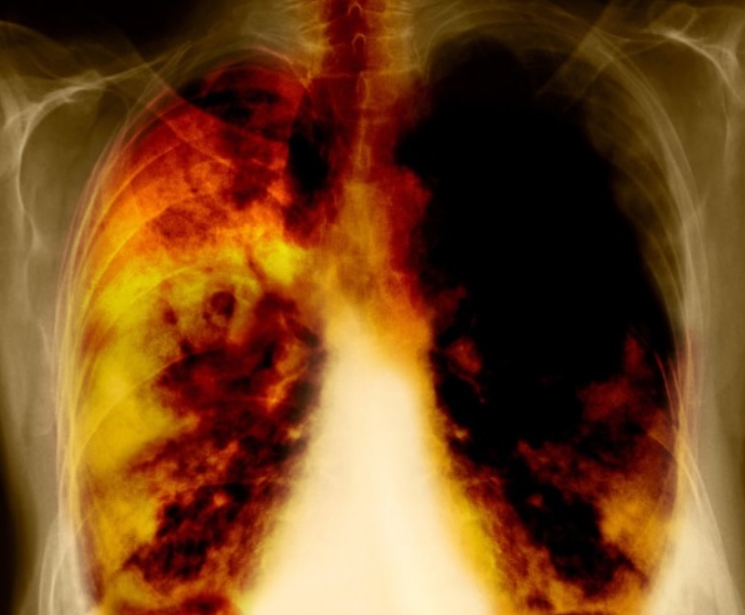

흉부CT는 말 그대로 가슴 속을 정밀하게 들여다보는 검사입니다. 예전에는 엑스레이로도 충분하다고 생각했지만, 지금은 보이지 않는 작은 변화들이 병을 가르는 시대가 되었죠. 실제로 제 지인은 계속 기침이 나서 감기인 줄 알았는데, 병원에서 흉부CT를 찍어보니 기관지염과 초기 폐렴이 동시에 진행 중이었습니다. 엑스레이로는 전혀 보이지 않던 부분이었어요.

이 검사는 X선을 여러 각도에서 투사해 가슴 속을 단면으로 나누고, 컴퓨터가 이를 조합해 입체적으로 보여줍니다. 흉부ct로 볼수있는 질환 폐, 기관지, 심장, 혈관, 흉막, 림프절, 늑골까지 모두 관찰할 수 있어요. 몸을 절개하지 않고 내부를 볼 수 있으니 환자에게 부담이 적습니다. 조영제(혈관이나 염증 부위를 선명하게 보여주는 약물)를 사용하는 경우에는 정맥으로 주입하기도 하지만, 대부분은 통증이 거의 없습니다.

엑스레이는 가볍고 빠른 검사예요. 병원에서 기침이나 흉통이 있으면 가장 먼저 찍는 사진이죠. 하지만 엑스레이는 가슴 속 장기를 한 번에 찍기 때문에, 여러 구조가 겹쳐 보입니다. 그만큼 정확한 구분이 어렵고, 미세한 결절이나 염증은 지나치기 쉽습니다.

흉부CT는 이야기가 달라요. 얇게 자른 단면을 수백 장 촬영하기 때문에, 작은 병변도 놓치지 않습니다. 마치 산 전체를 한 장의 사진으로 보는 엑스레이와 달리, CT는 나무 한 그루 한 그루를 자세히 보는 느낌이에요. 예전에 병원에서 일했던 친구 말로는, 엑스레이에 아무 이상이 없던 환자가 CT에서 폐암 초기 진단을 받은 경우도 많았다고 합니다. 그만큼 CT는 정밀한 탐색 도구입니다.